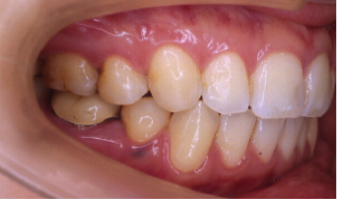

叢生(そうせい)

20歳/女性

悩み:歯がデコボコ

八重歯が押し出されて歯がでこぼこに並んでいる状態

治療期間:約2年4ヶ月

治療前

奥の歯が倒れて狭くなっている台形の歯列を広げて歯を起こす治療で、奥の歯が見えるようになるUの字型に治しました。

上の歯下の歯、それぞれ2本づつ第一小臼歯を抜歯した治療となりました。

歯を見せて笑えるようになり喜んでもらいました。